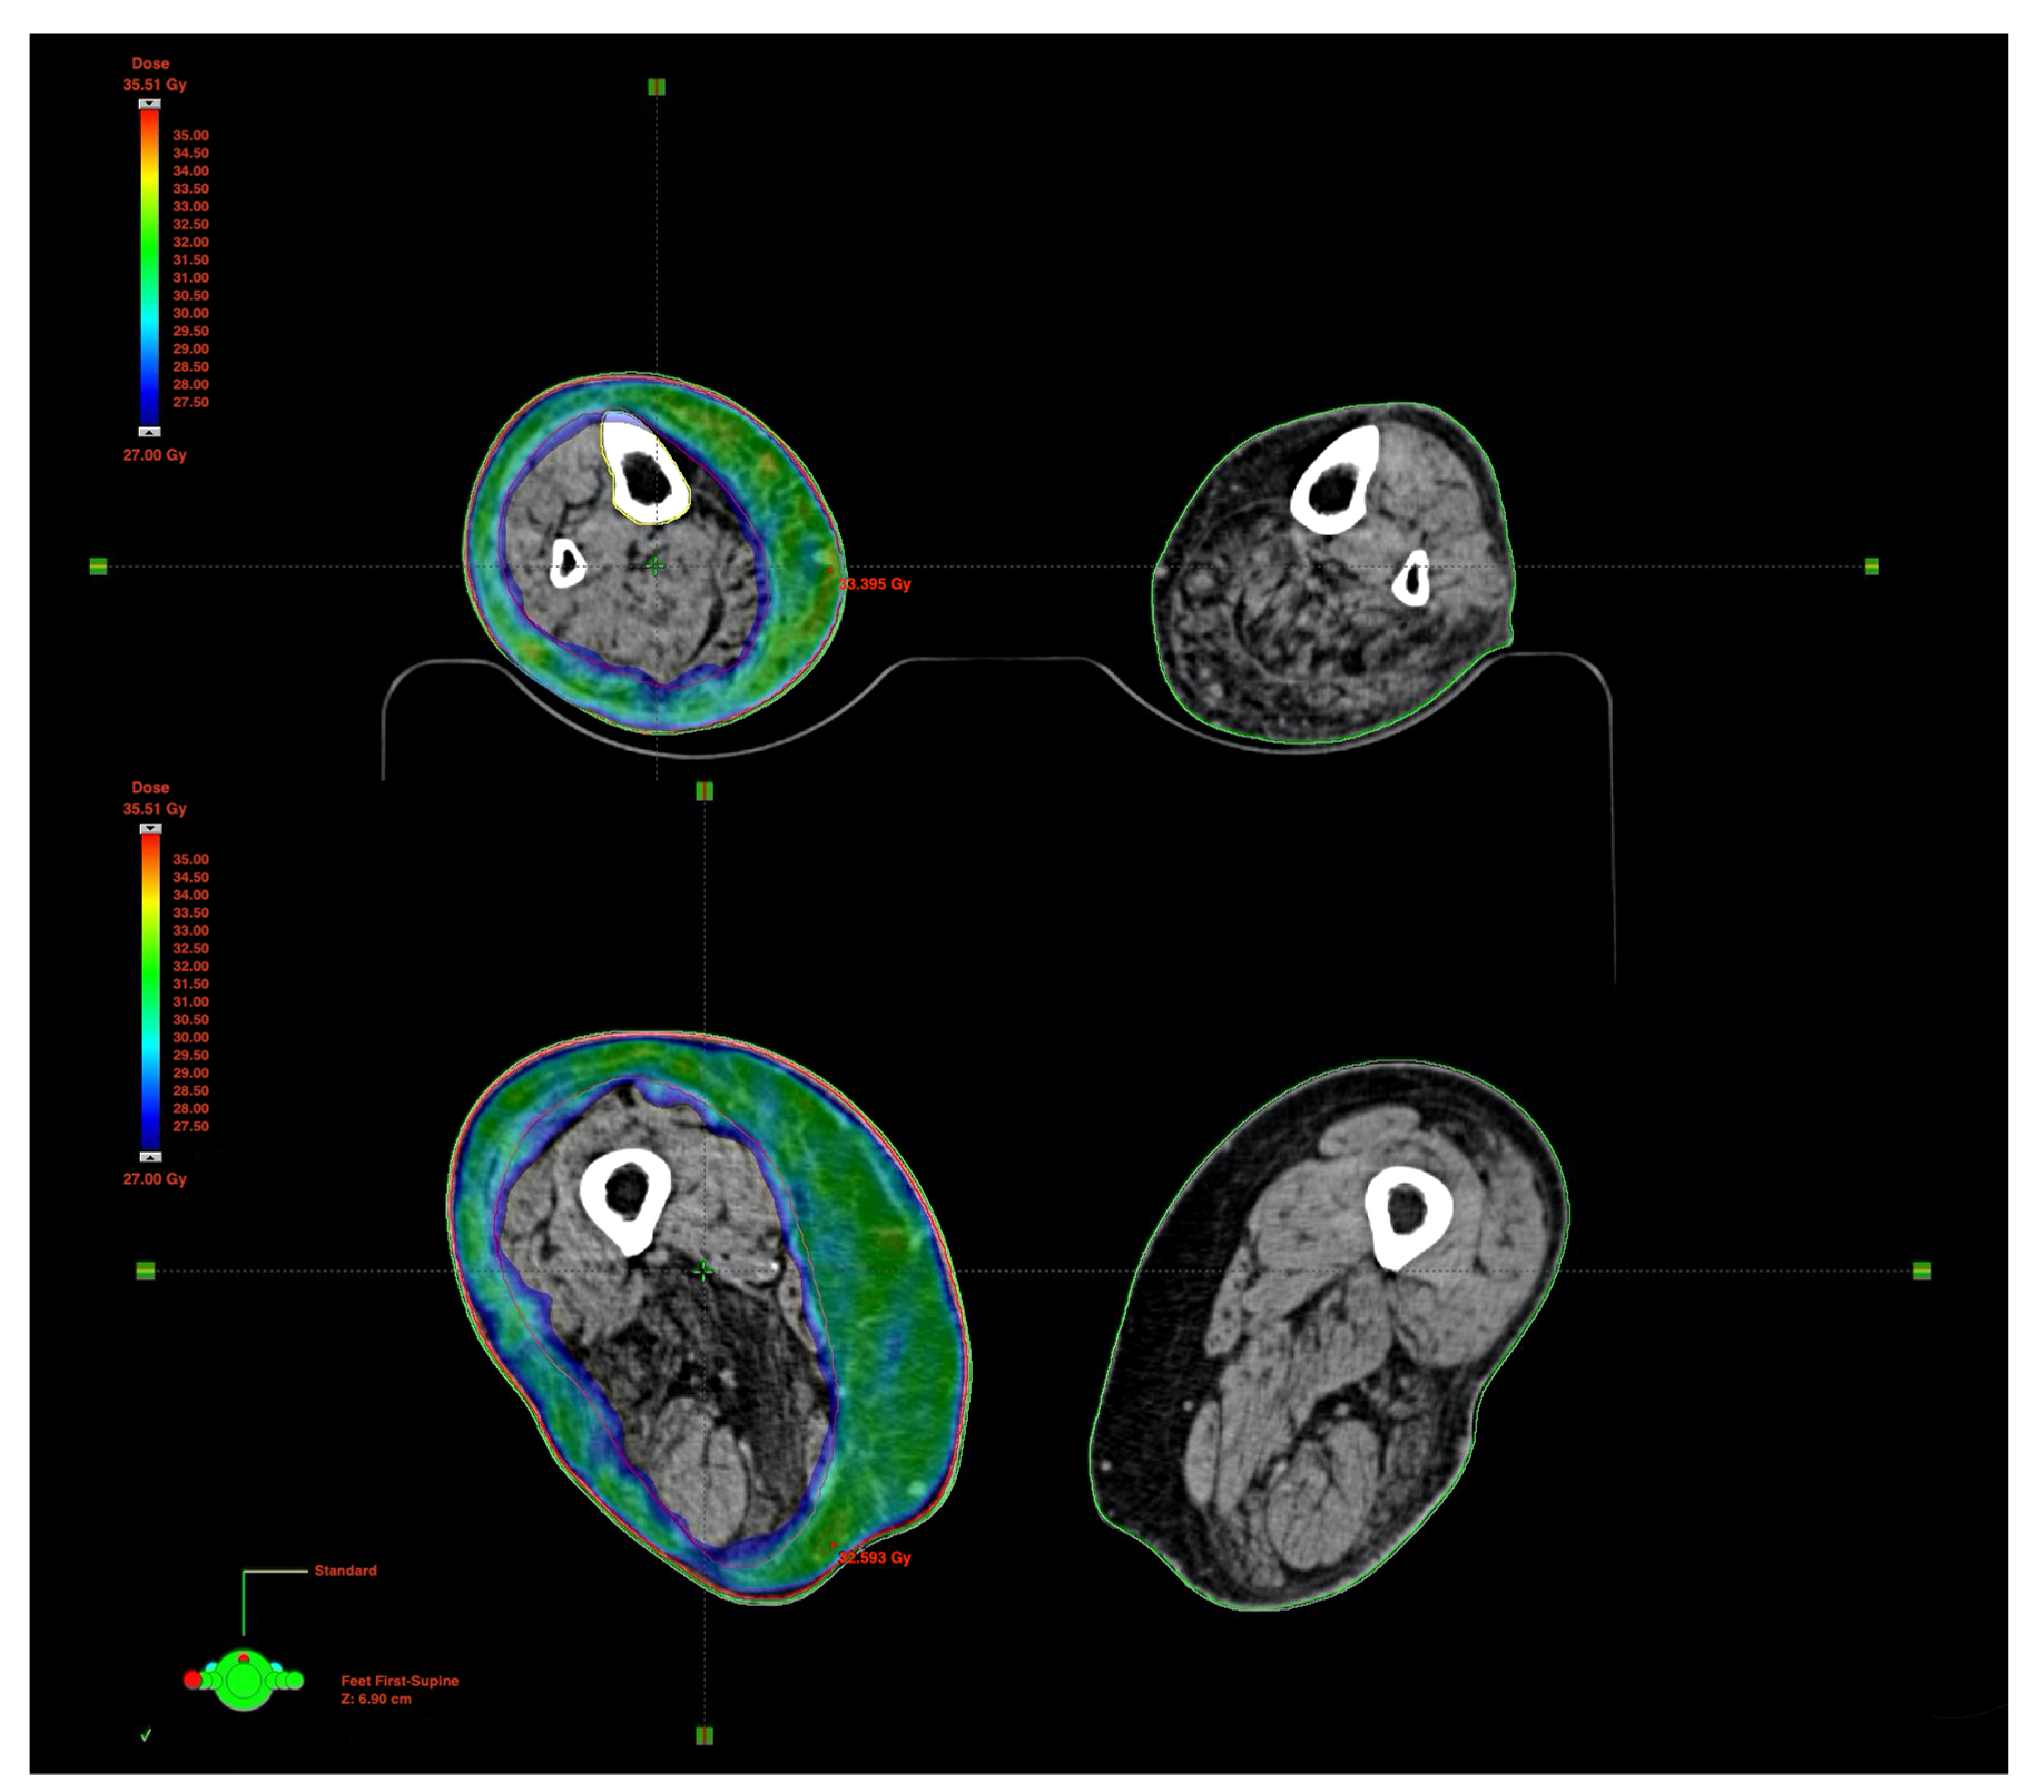

2. Case Study